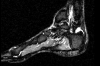

After reviewing radiographs and magnetic resonance imaging (MRI), I was able to establish that she most likely was suffering from a true Haglund’s deformity. Before resorting to surgical intervention, I made an attempt to work with her training patterns. We had her slow her pace down and follow her aerobic pace (her heart rate was well below lactic threshold, which for her was 137 beats per minute (BPM) to ensure she was not overdoing it. She was concerned that she would not be able to get her heart rate this high but after her first run under monitoring, she was blown away to find out how slow she had to run to keep her heart rate this low. While this may not seem important to most practitioners, running too hard too often can lead to overuse injuries, which then get stuck in the chronic phase. She adhered to this principle of training for almost six months before we elected to surgically resect the prominent Haglund’s deformity due to her continued pain with running.

After reviewing radiographs and magnetic resonance imaging (MRI), I was able to establish that she most likely was suffering from a true Haglund’s deformity. Before resorting to surgical intervention, I made an attempt to work with her training patterns. We had her slow her pace down and follow her aerobic pace (her heart rate was well below lactic threshold, which for her was 137 beats per minute (BPM) to ensure she was not overdoing it. She was concerned that she would not be able to get her heart rate this high but after her first run under monitoring, she was blown away to find out how slow she had to run to keep her heart rate this low. While this may not seem important to most practitioners, running too hard too often can lead to overuse injuries, which then get stuck in the chronic phase. She adhered to this principle of training for almost six months before we elected to surgically resect the prominent Haglund’s deformity due to her continued pain with running.

This case concerns a 43-year-old female runner who had dealt with pain in her posterior Achilles tendon and heel for five years. She had been a distance runner for over 30 years and had exhausted all forms of conservative therapy consisting of non-steroidal anti-inflammatory drugs (NSAIDs), rest, physical therapy, deep tissue massage, pressure point management and finally eight weeks in a controlled ankle motion (CAM) walker. She got a referral to me from a fellow colleague who thought she may need surgery and we began initial contact via email as she was far from my office. After reviewing radiographs and magnetic resonance imaging (MRI), I was able to establish that she most likely was suffering from a true Haglund’s deformity. Before resorting to surgical intervention, I made an attempt to work with her training patterns. We had her slow her pace down and follow her aerobic pace (her heart rate was well below lactic threshold, which for her was 137 beats per minute (BPM) to ensure she was not overdoing it. She was concerned that she would not be able to get her heart rate this high but after her first run under monitoring, she was blown away to find out how slow she had to run to keep her heart rate this low. While this may not seem important to most practitioners, running too hard too often can lead to overuse injuries, which then get stuck in the chronic phase. She adhered to this principle of training for almost six months before we elected to surgically resect the prominent Haglund’s deformity due to her continued pain with running.

After reviewing radiographs and magnetic resonance imaging (MRI), I was able to establish that she most likely was suffering from a true Haglund’s deformity. Before resorting to surgical intervention, I made an attempt to work with her training patterns. We had her slow her pace down and follow her aerobic pace (her heart rate was well below lactic threshold, which for her was 137 beats per minute (BPM) to ensure she was not overdoing it. She was concerned that she would not be able to get her heart rate this high but after her first run under monitoring, she was blown away to find out how slow she had to run to keep her heart rate this low. While this may not seem important to most practitioners, running too hard too often can lead to overuse injuries, which then get stuck in the chronic phase. She adhered to this principle of training for almost six months before we elected to surgically resect the prominent Haglund’s deformity due to her continued pain with running.